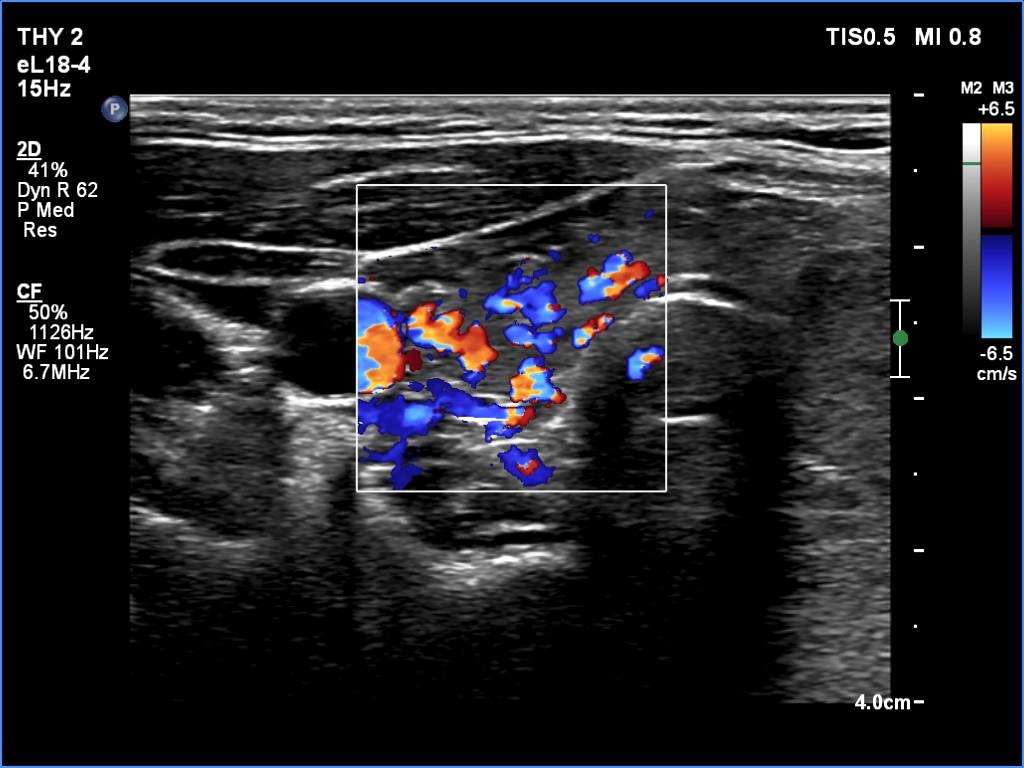

The echogenicity of the nodule - case 365 (ultrasonographic picture 3)

Seven years after the first examination

Right lobe, transverse scan, color Doppler mode. The vascularity became increased.